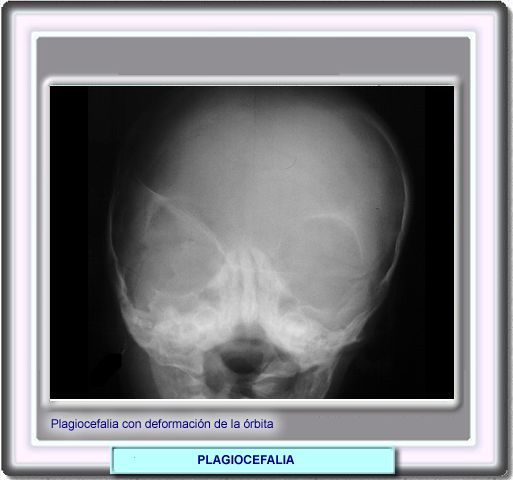

El síndrome de Ruvalcaba-Myhre-Smith es una enfermedad hereditaria rara, caracterizada por un crecimiento excesivo previo y posterior al nacimiento, macrocefalia, plagiocefalia escafocefalia, inteligencia normal o retraso mental leve, y crecimientos tumorales benignos preferentemente subcutáneos, similares al hamartoma.